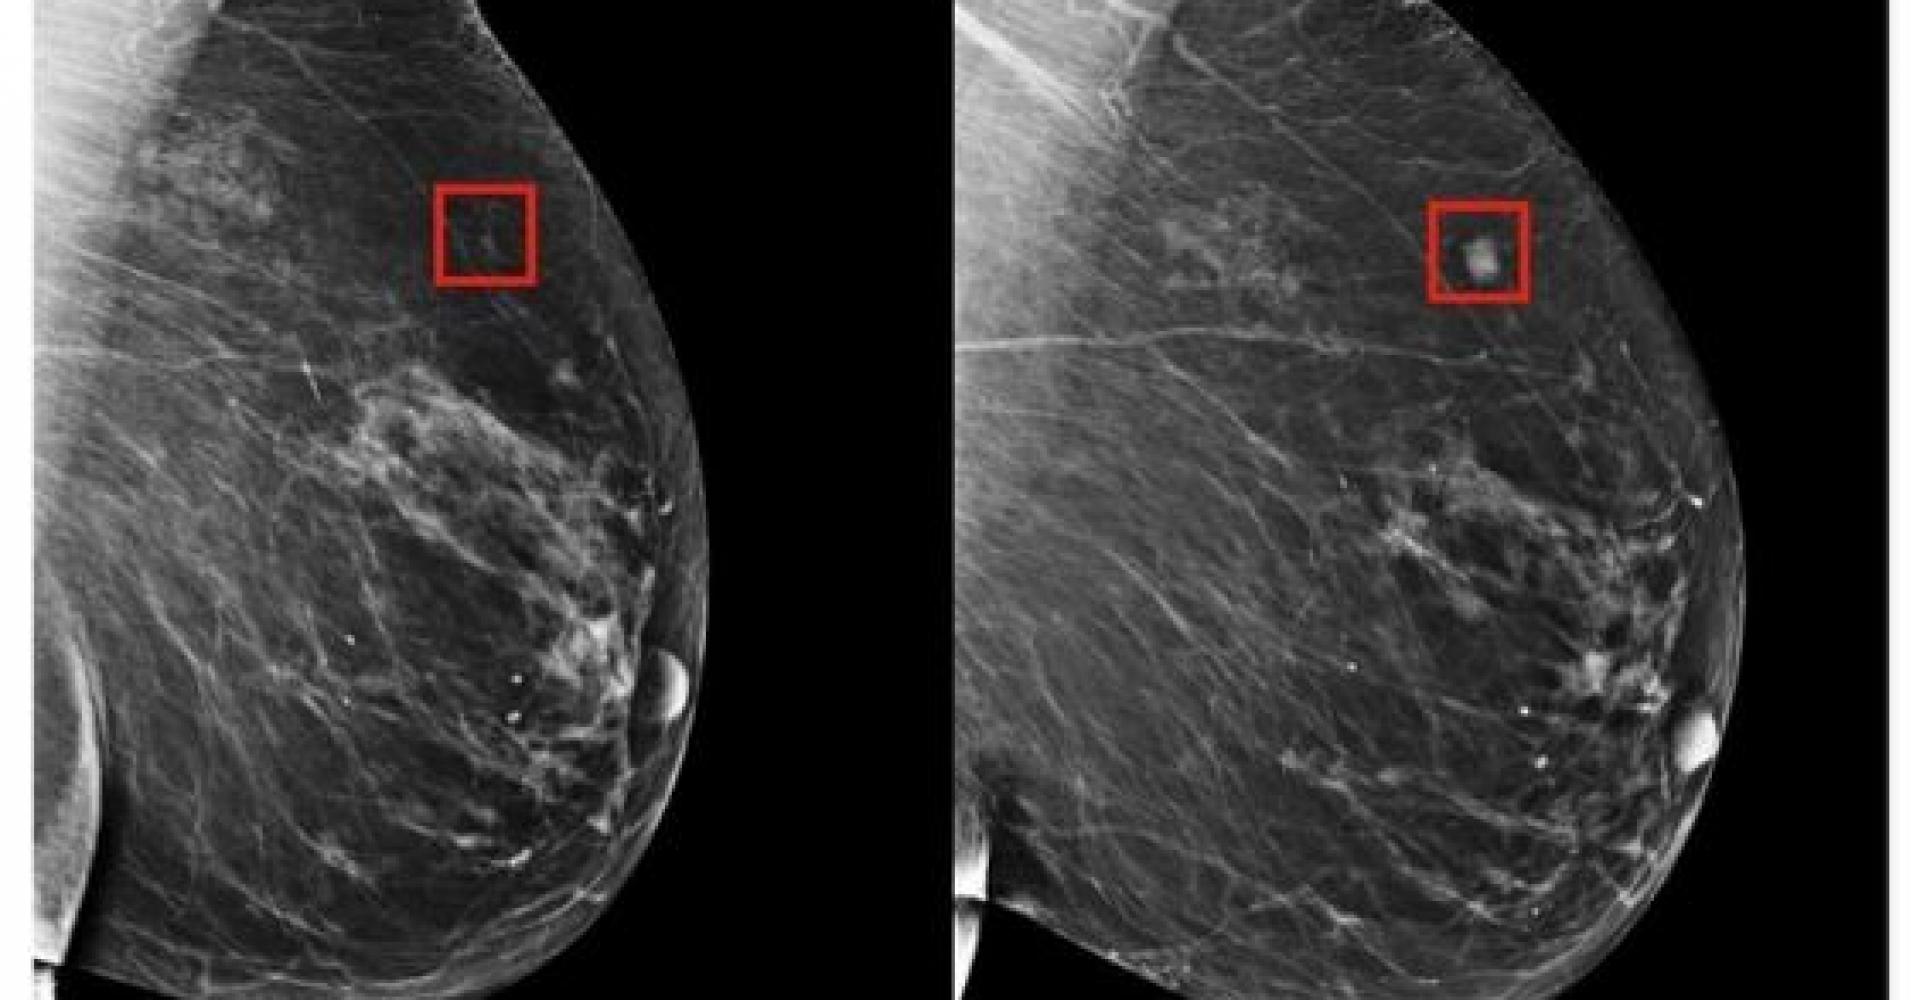

Com isso em mente, uma equipe do Laboratório de Ciência da Computação e Inteligência Artificial do MIT e do Hospital Geral de Massachusetts (MGH) criou um novo modelo de aprendizagem profunda que pode prever a partir de uma mamografia se um paciente desenvolver câncer de mama como cinco anos no futuro.

Em vez de identificar manualmente os padrões em uma mamografia que conduzem o câncer futuro, a equipe do MIT / MGH treinou um modelo de aprendizagem profunda para deduzir os padrões diretamente dos dados. Usando informações de mais de 90.000 mamografias, o modelo detectou padrões muito sutis para o olho humano detectar.